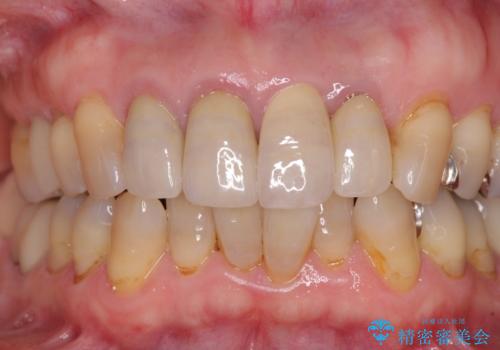

1. 折れてしまった前歯 インプラントによる補綴治療の治療前

3. 折れてしまった前歯 インプラントによる補綴治療の治療後